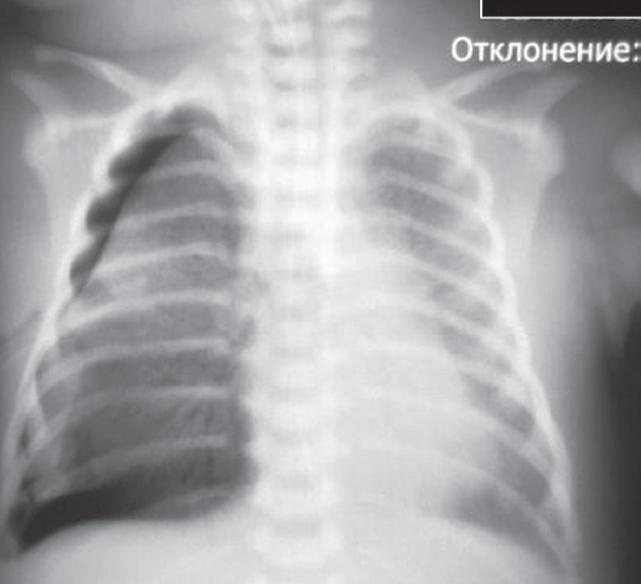

The article presents a case of successful treatment of acute respiratory distress syndrome in a full-term newborn complicated by pulmonary barotrauma using monobronchial administration of exogenous surfactant under X-ray control. In order to assess the course of the disease and the effectiveness of treatment, a retrospective analysis of medical documentation was carried out. From the first minutes of life, the child had respiratory disorders, which was the basis for non-invasive mechanical lung ventilation — nCPAP (nasal continuous positive airway pressure). Progression of hypercapnia and hypoxemia was revealed over time, and therefore tracheal intubation was performed and convective mechanical ventilation was started with FiO2 = 1,0. Monobronchial administration of exogenous surfactant was a key element of the therapy that allowed to achieve stabilization of the condition and regression of gas exchange disorders with complete recovery of the patient.

Monobronchial administration of surfactant in acute respiratory distress syndrome with heterogeneous lung involvement is an effective treatment option and can be used in clinical practice for refractory hypoxemia.